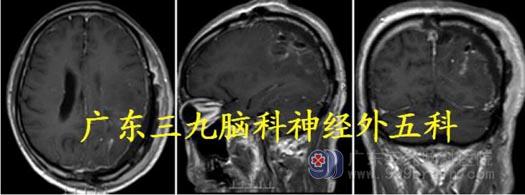

入院诊断:左侧顶枕部占位病变:考虑脑膜瘤;

头颅CT:左侧顶部占位性病变,并周围广泛水肿,邻近左侧顶骨受侵犯,考虑脑外占位性病变。

头颅MR:左侧顶部示团块状占位性病变,范围约5.5×6.0×6.4cm,增强扫描明显强化,左侧顶部占位性病变伴病灶内及周围多发畸形血管,考虑脑膜瘤可能性大,不排除近脑表面胶质肉瘤并血管畸形;

取左侧颞顶枕马蹄形切口,脑表面许多异常增生血管,可见肿瘤组织与硬脑膜粘连,肿瘤表面大量异常血管,先电灼、分离肿瘤基底部,沿肿瘤边缘分离,肿瘤质中,包膜完整。完整全切肿瘤,前后主要上吻合静脉保护良好。

术后头颅MR 显示肿瘤完整切除。病理:脑膜皮细胞型脑膜瘤,WHO I 级。